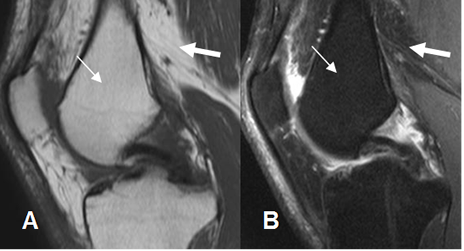

Fig 1. Medula ósea en adulto normal

A: RM sagital en T1 y B: RM sagital en STIR. La señal de la medula osea amarilla (Flecha delgada), es similar a la de la grasa (Flecha gruesa).